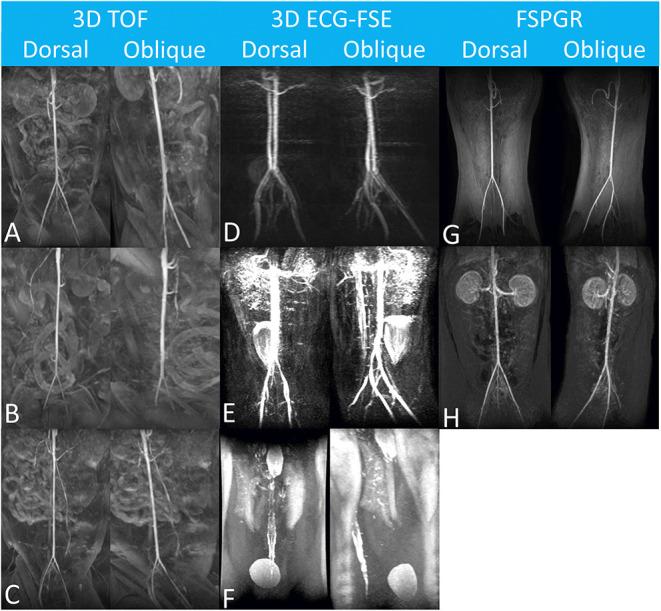

Arterial thromboembolism is associated with high morbidity and mortality rates in cats. Definitive diagnosis requires advanced imaging modalities, such as computed tomography angiography (CTA) and contrast-enhanced (CE) magnetic resonance angiography (MRA). However, CTA involves exposure to a large amount of ionized radiation, and CE-MRA can cause systemic nephrogenic fibrosis. Non-contrast-enhanced (NE) MRA can help accurately diagnose vascular lesions without such limitations. In this study, we evaluated the ability of NE-MRA using three-dimensional electrocardiograph-gated fast spin-echo (3D ECG-FSE) and 3D time-of-flight (3D TOF) imaging to visualize the aorta and external iliac arteries in clinically healthy cats and compared the results with those obtained using CE-MRA. All 11 cats underwent 3D ECG-FSE, 3D TOF, and CE-MRA sequences. Relative signal intensity (rSI) for quantitative image analysis and image quality scores (IQS) for qualitative image analysis were assessed; the rSI values based on the 3D TOF evaluations were significantly lower than those obtained using 3D ECG-FSE (aorta 3D TOF: 0.57 ± 0.06, aorta 3D ECG-FSE: 0.83 ± 0.06, < 0.001; external iliac arteries 3D TOF: 0.45 ± 0.06, external iliac arteries 3D ECG-FSE:0.80 ± 0.05, < 0.001) and similar to those obtained using CE-MRA (aorta: 0.58 ± 0.05, external iliac arteries: 0.57 ± 0.03). Moreover, IQS obtained using 3D TOF were significantly higher than those obtained using 3D ECG-FSE (aorta 3D TOF: 3.95 ± 0.15, aorta 3D ECG-FSE: 2.32 ± 0.60, < 0.001; external iliac arteries 3D ECG-FSE: 3.98 ± 0.08, external iliac arteries 3D ECG-FSE: 2.23 ± 0.56, < 0.001) and similar to those obtained using CE-MRA (aorta: 3.61 ± 0.41, external iliac arteries: 3.57 ± 0.41). Thus, 3D TOF is more suitable and produces consistent image quality for visualizing the aorta and external iliac arteries in clinically healthy cats and this will be of great help in the diagnosis of FATE.